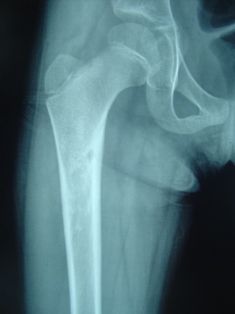

The child will complain of severe pain in the bone or near joint at night which is relieved by analgesic (combiflam). The pain is so severe that the child will wake up at night and cry and will stop only after pain medication is given. This will not be related to activity and will happen on a daily basis. It is a benign lesion. Radiograph will show a nidus surrounded by sclerotic bone. CT scan may be required for diagnosis. Surgical excision of nidus is indicated and it gives immediate relief. The patient will have no pain from the next day of surgery. Radio frequency ablation of lesion is also being done in select centers for specific location.